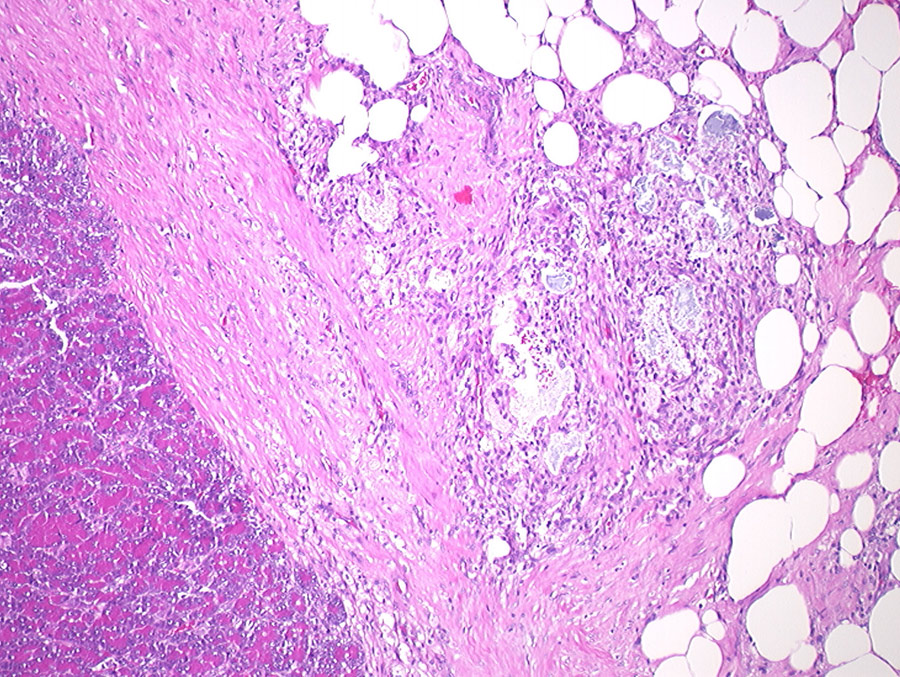

纽曼研究兴趣还伸展到诊断各种动物的胰岛素疾病上,犬巢病难以诊断,原因是缺乏高度具体敏感测试,尽管在她生涯中已经实现这一点。Pancriatis是最常见的狗排尿孔病之一 — — 也是发病和死亡的重要原因之一。狗肠炎分类系统上次更新于1992年,内含封膜炎类型定义模糊慢性胰炎是一种慢性炎,会影响周围组织并可能永久损害导致纤维化(组织萎缩)的脉冲急性胰炎是一种急性炎,引起点细胞死亡和消化酶渗入周围腹部脂肪,并产生配方化(烟雾编组),这是一种特征历史变换后者通常还伴生腹痛

少数研究报告狗脉炎骨折,直到纽曼哨点工作评价大量狗与此条件相关联的炎症局部化、纤维化和死死Newman解析狗死后研究中这些前未探索因素,通过她的研究 疾病进程正得到更好的特征化 提高胰岛炎诊断精度

值得注意的是 纽曼显示狗肠炎 随机分布损耗因此,她建议多段封口评估死或发炎变化,包括死前和死后变化Newman强调需要功能分级系统描述肠炎特征以改善诊断和预测疾病,从验尸研究中可以看出单片切片是不够的。开发改良狗排气管炎诊断系统目前构成猫类类似研究基础